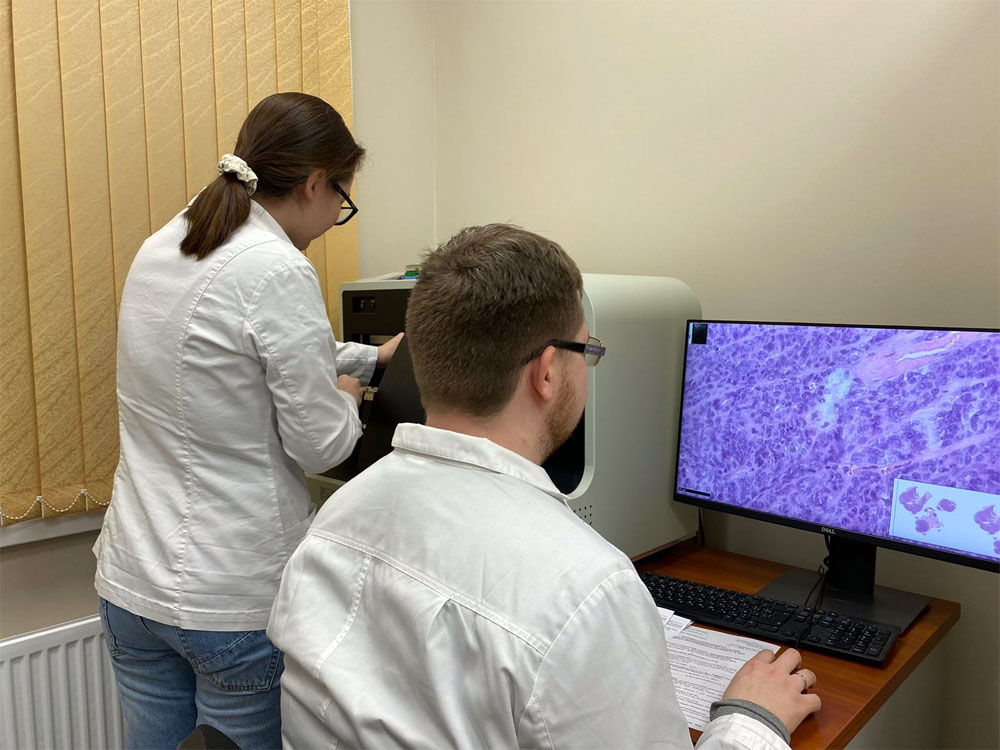

Пироговский Центр продолжает реализовывать план мероприятий в рамках федерального проекта «Борьба с онкологическими заболеваниями»

Благодаря участию Центра в федеральном проекте «Борьба с онкологическими заболеваниями» ряд отделений Центра получили новое оборудование, необходимое для диагностики и лечения пациентов с подозрением или уже выявленным злокачественным новообразованием. В 2022 году запланирована организация Отделения лучевой терапии Центра.